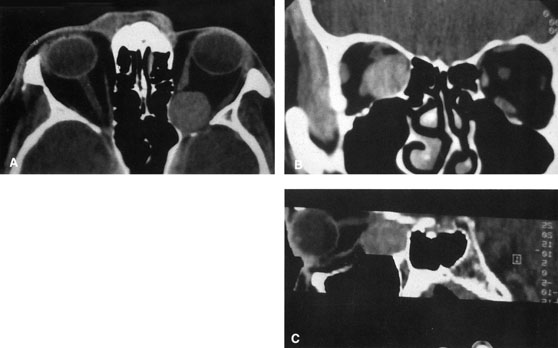

Lateral orbitotomy provides excellent access to deep lesions in the subperiosteal, peripheral, or intraconal space lateral to the optic nerve (Fig. 8A, B).

Fig. 8. Coronal (A) and axial (B) views in an illustration of areas (shaded) amenable to lateral orbitotomy.

Although intraconal lesions medial to the nerve sometimes can be approached laterally, great care to identify and protect the optic nerve is required during deep orbital dissection. Because the eyelid crease incision allows such wide exposure of the superolateral orbit, it is often possible to remove fairly large orbital lesions without removing the lateral orbital wall (Fig. 9). Surgery in this case proceeds as described to exposure of the superior and lateral bony orbital rims. It is not necessary to reflect periosteum over the external surface of the rim. Instead, once periosteum at the rim is exposed, it is cut with cautery and then only the mesial periorbita need be elevated internally to expose orbital contents with subsequent intra-orbital dissection carried out with the lateral rim in place. Often it is preferable to initially attempt to remove intraconal or lacrimal fossa lesions in this fashion. If exposure proves inadequate, the periosteum over the external surface of the lateral orbital rim can be elevated and osteotomies and removal of the lateral wall still can be carried out.

Fig. 9. A,B. Coronal and axial CT images of a large intraconal neoplasm. C. Because it was felt to represent a well-encapsulated cavernous hemangioma, this lesion was a candidate for removal via an eyelid crease orbitotomy without bone removal. The eyelid crease incision marked. D. Incision made with scalpel. E. Orbicularis muscle is tented up and incised to expose the underlying septum. F. Dissection of a skin-muscle flap deep to orbicularis exposes the orbital septum and superior orbital bony rim. G. Cutting cautery is used to incise periosteum along the superior and lateral rims; finger palpation of the bone helps to direct this incision. H. Periorbita is elevated along the mesial surface of the lateral orbital rim in order to expose the deep orbital tissues. I. The cavernous hemangioma is visualized in the wound. Retraction is provided by one or more malleable retractors. J. Cryoprobe is affixed to the hemangioma to facilitate manipulation of the lesion. K. Large cavernous hemangioma after removal through the eyelid crease incision which was accomplished without bone removal. L. Periorbita is reattached over the lateral rim. M. The eyelid crease incision is closed with a running suture.